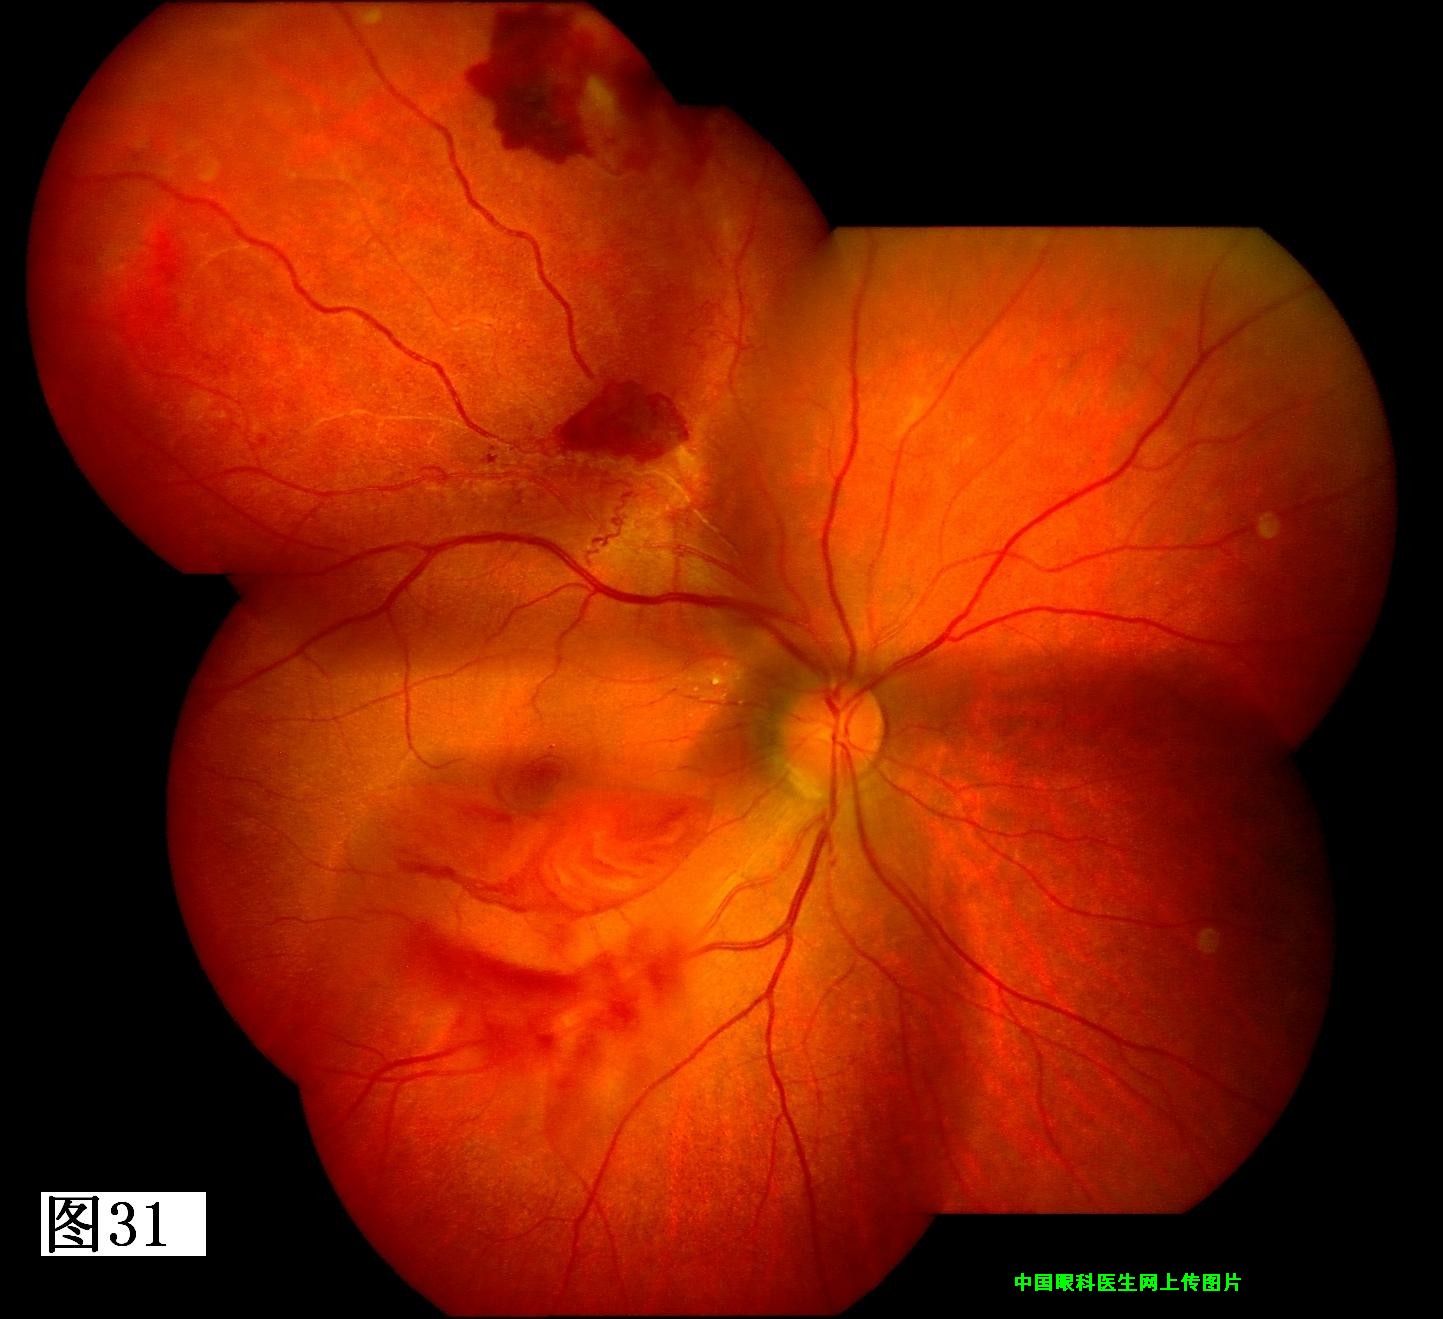

29 30 31 32